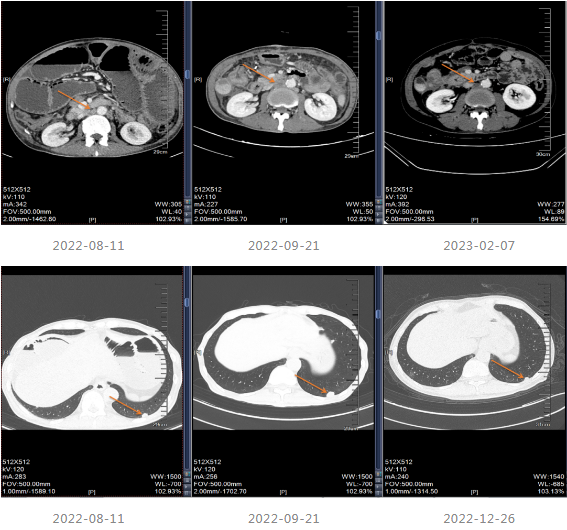

2019-03-14行上腹部增强CT,显示肝内散在的多发圆形稍低密度灶,大小不等,边界欠清晰,较大者直径约5.2cm,其内密度不均,增强扫描病灶周边有强化,内部有更低密度区液化坏死区,考虑转移瘤;胆囊多发结石;双肾多发结石,直径小于0.2cm;扫描范围内结肠肝区管壁增厚,管腔狭窄,增强扫描可见明显强化。

局部治疗:2020-09-26复查MRI提示部分病灶较前缩小,部分增大,于2020-10-22至武汉同济医院行“肝脏病灶微波消融术”,后继续口服卡培他滨至2021-5。

2022-04至2022-07采用“贝伐珠单抗联合卡培他滨”维持治疗4周期,维持治疗期间患者渐感腹胀伴消瘦。

202-08出现肠梗阻,内科治疗效果不佳。

2022-08-29至武汉同济医院行小肠造瘘术。

▌四线治疗

患者出现肠梗阻,考虑病情PD,因此2022-10-06至今采用“斯鲁利单抗(200mg q3w)+呋喹替尼(4mg/d,口服,服3周停1周)”进行治疗,治疗过程中患者一般情况良好,体重增加。